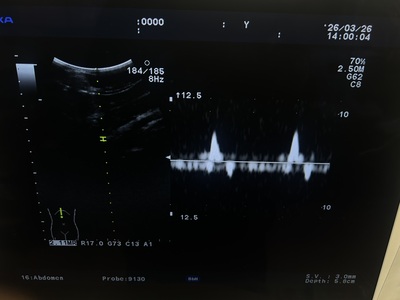

Ultrasound System

Ultrasound